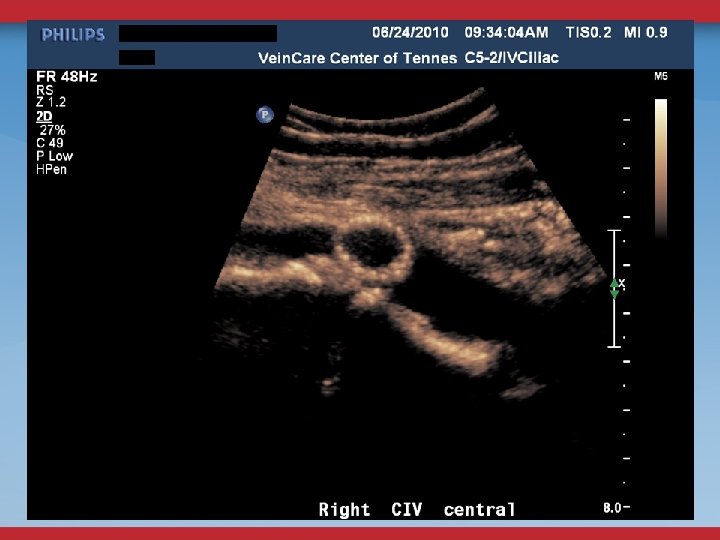

DEFINITIVE DIAGNOSTIC/THERAPEUTIC PROCEDURES VENOGRAMS UG sheath placement Femoral, Pop, PTV Flow, Collaterals

VENOGRAMS FEMORAL INFLOW FILLING DEFECTS WILL MISS SOME STENOSES, WEBS

INTRAVASCULAR ULTRASOUND THE ANATOMIC GOLD STANDARD USUALLY BILATERAL IFV/IVC CHOOSE DIAMETER/LENGTH OF BALLOON/STENT POST-STENTING ASSESSMENT